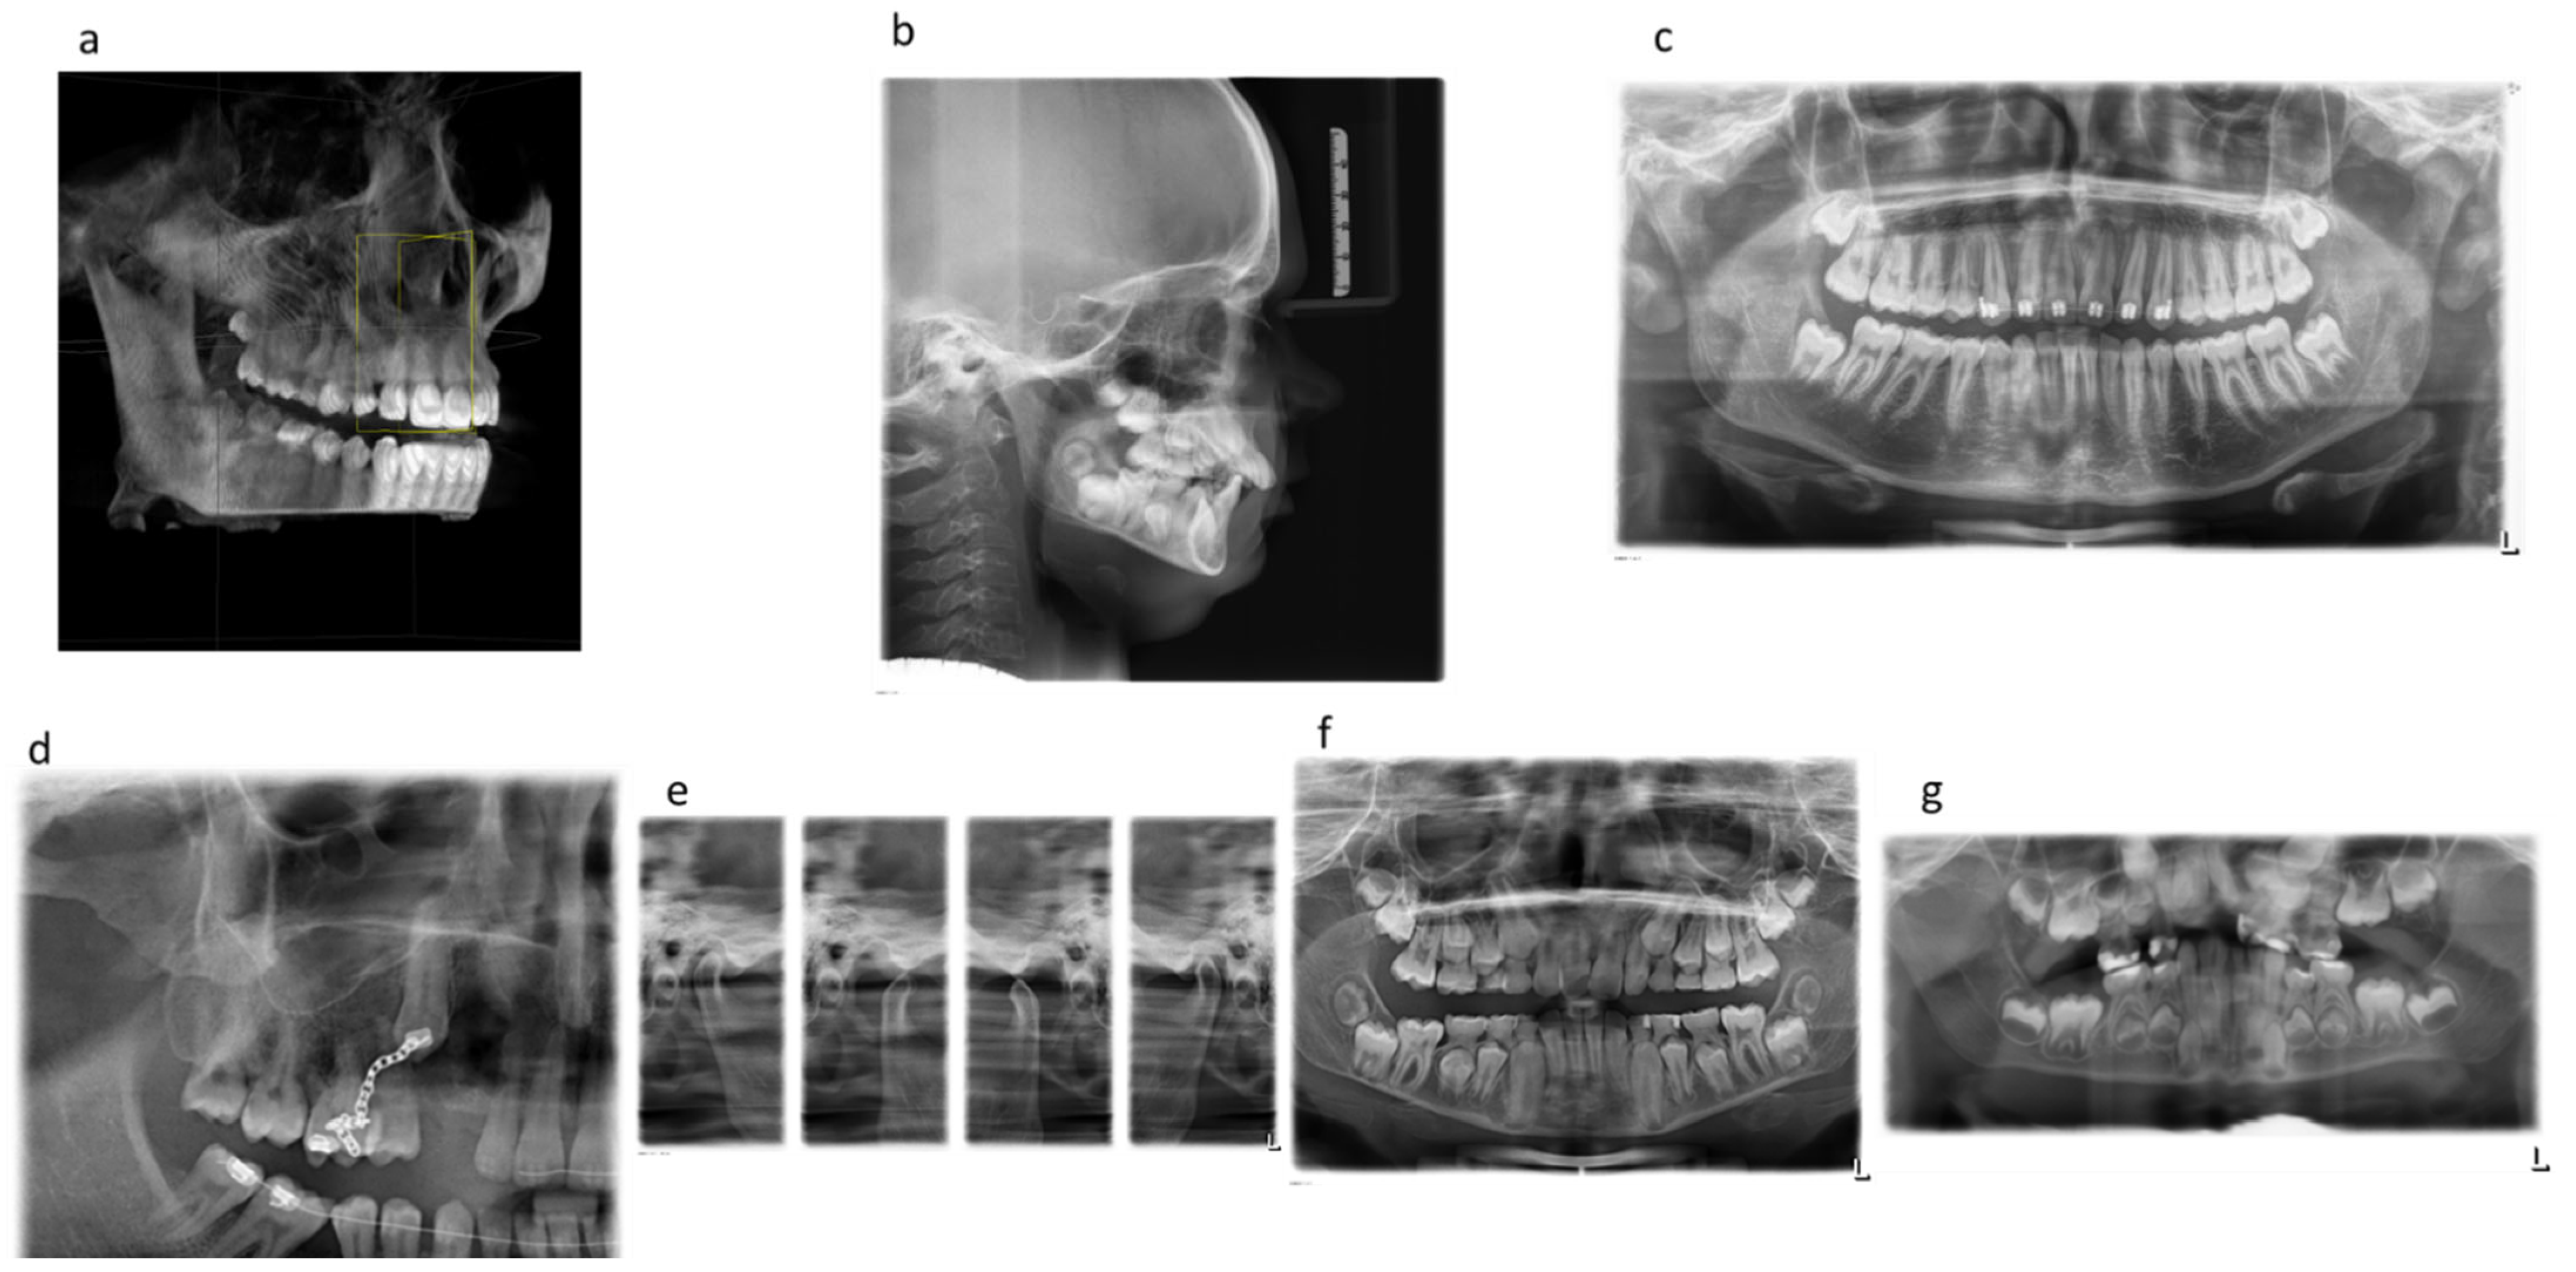

Beyond diagnosis, regular imaging plays a vital role in treatment planning. Whether you're considering braces or implants or undergoing root canal therapy, precise images enable personalized care tailored to your unique anatomy.

The evolution from traditional film-based radiographs to digital sensors has revolutionized how we approach dental diagnostics. Digital radiography offers numerous advantages over its predecessor: faster processing times leading to shorter appointments; enhanced image quality for better diagnoses; less environmental impact without chemical processing; and easier storage and sharing capabilities which facilitate patient education and interdisciplinary communication.

The evolution of dental x-ray technology has been significant, with modern digital x-rays reducing radiation exposure by up to 90% compared to traditional film-based systems. Understanding the advancements in dental radiography is crucial for patients who are concerned about safety. Digital radiography not only minimizes radiation but also provides clearer images for better diagnosis, which can be enhanced and analyzed instantly.

Dental x-rays also serve as a critical tool in planning complex dental treatments such as orthodontics, implants, and extractions. The detailed imagery helps create precise treatment plans tailored to each patient's unique anatomy. To explore how modern technology is shaping these plans, visit our page on digital dentistry benefits.

- 3D Cone Beam CT Imaging - Provides detailed images for precise diagnosis and treatment planning.